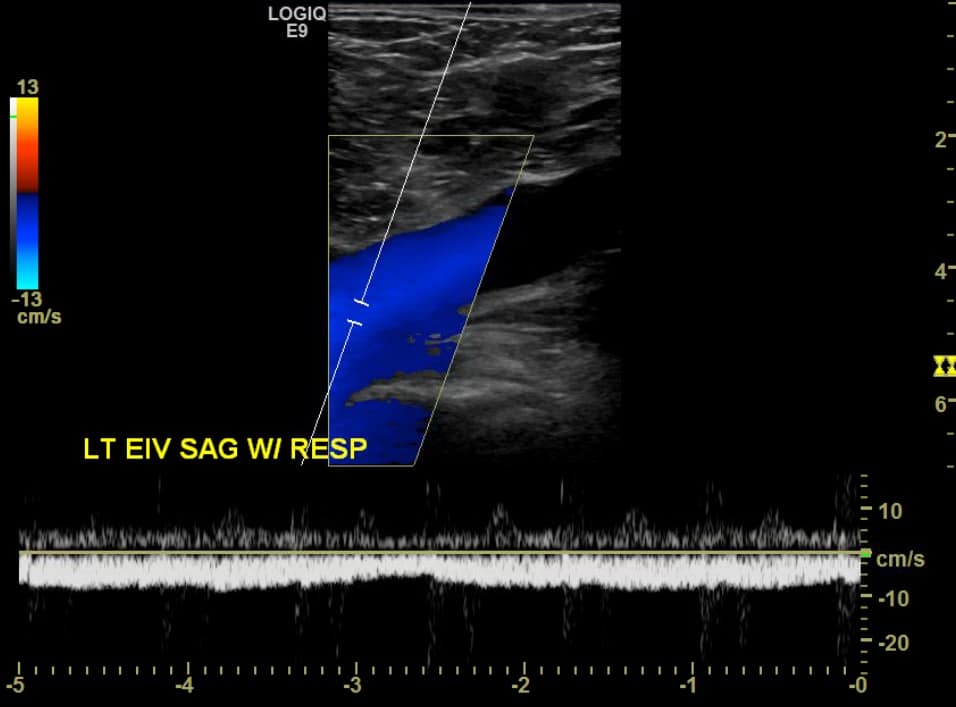

The use of Doppler imaging can be used on a selected basis but is not a required component of the proximal LE compression ultrasound. The routine use of augmentation has not been shown to improve sensitivity or specificity for the detection of proximal LE DVTs.5,6 When a proximal iliofemoral DVT is suspected, spectral Doppler of the CFV can be performed to assess for respiratory variation (Figure 12). Respiratory variation will be absent in patients with complete iliofemoral occlusion.

Figure 12. Sagittal window of common femoral vein (CFV) with spectral Doppler demonstrating normal respiratory variation.